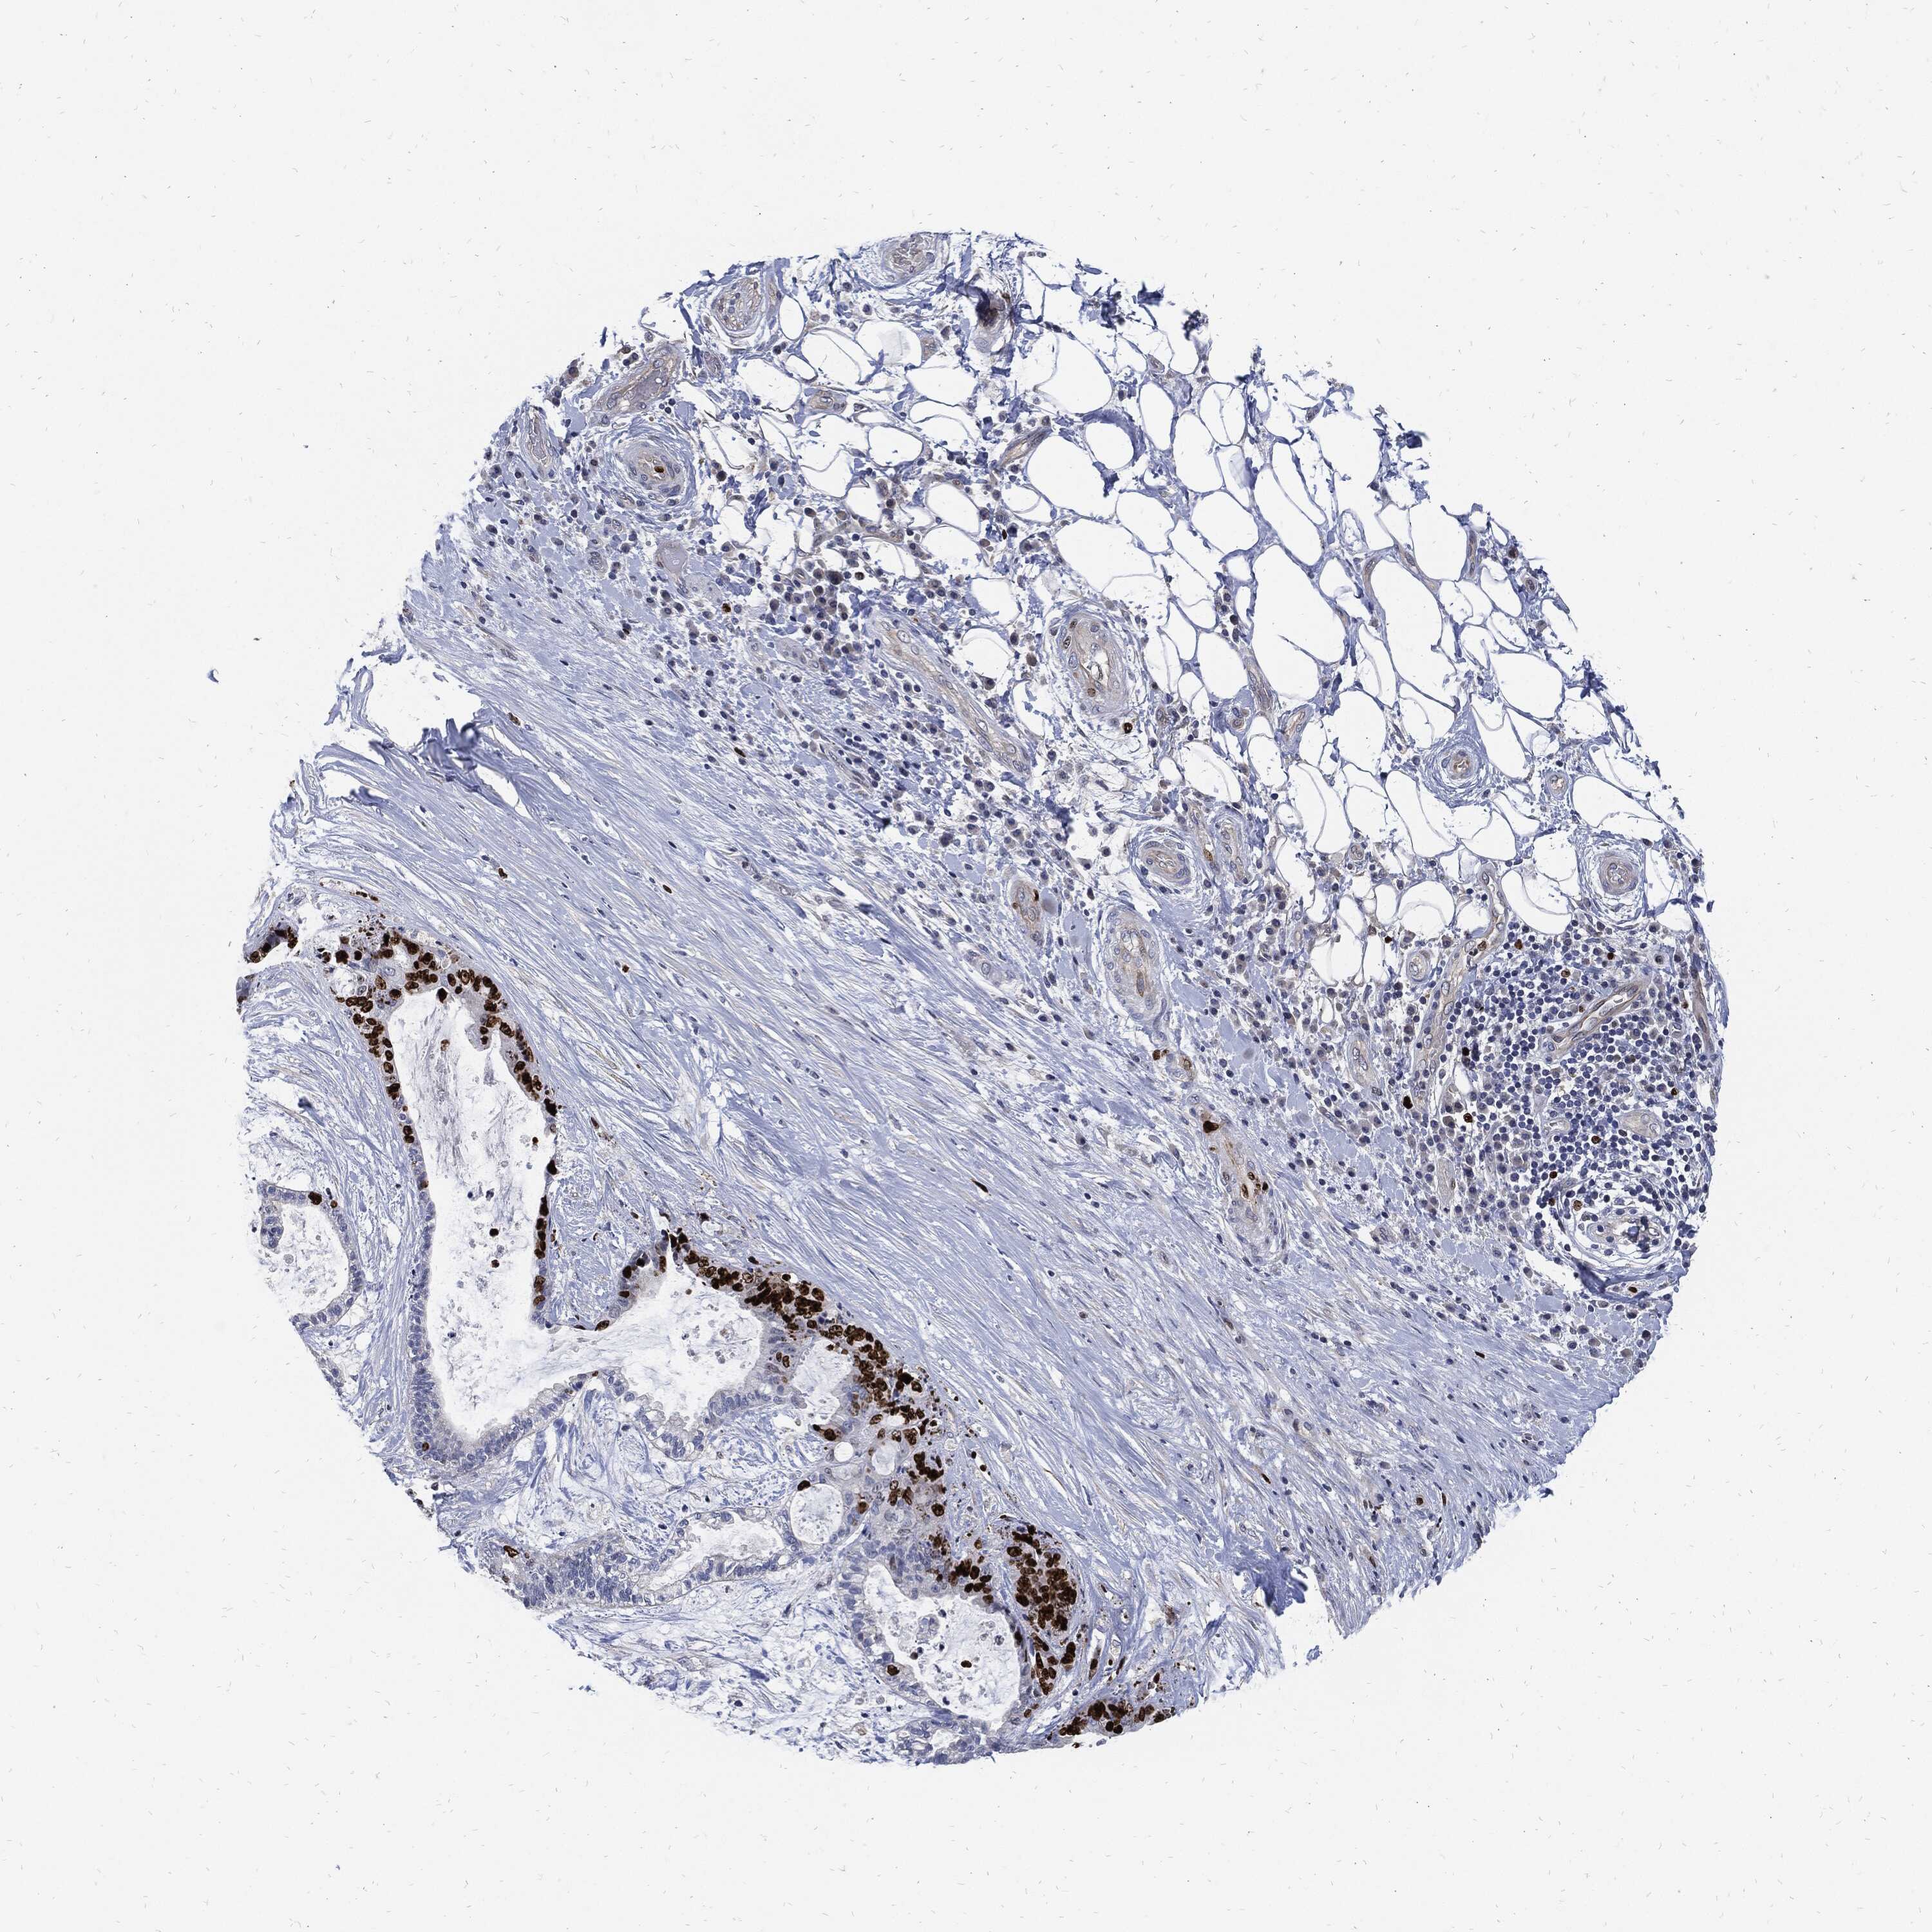

LIVER CANCER - Protein expressioni

A mouse-over function shows sample information and annotation data. Click on an image to view it in a full screen mode. Samples can be filtered based on level of antibody staining by selecting one or several of the following categories: high, medium, low and not detected. The assay and annotation is described here.

Note that samples used for immunohistochemistry by the Human Protein Atlas do not correspond to samples in the TCGA dataset.

Antibody stainingi

Antibody staining in the annotated cell types in the current human tissue is reported as not detected, low, medium, or high, based on conventional immunohistochemistry profiling in selected tissues. This score is based on the combination of the staining intensity and fraction of stained cells.

Each image is clickable and will lead to virtual microscopy that enables deeper exploration of all samples and also displays staining intensity scores, fraction scores and subcellular localization as well as patient and tissue information for each sample.

Carcinoma, Hepatocellular, NOS

Cholangiocarcinoma